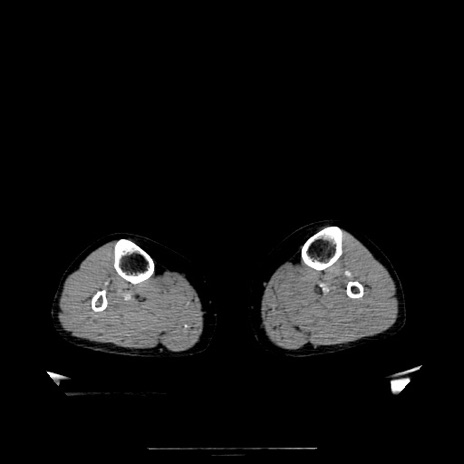

【症例】70歳代女性

【主訴】お腹が張る

【現病歴】1週間くらい前から腹部膨満の自覚あり。昨日夜から増悪したため、本日救急外来受診。

【身体所見】意識清明、BT 36.5℃、BP 165/106mmHg、HR 80bpm、SpO2 98%、腹部:膨満、軟、自発痛・圧痛なし、触診にて不快感あり、腸蠕動音:減弱

【データ】WBC 12600、CRP 1.04